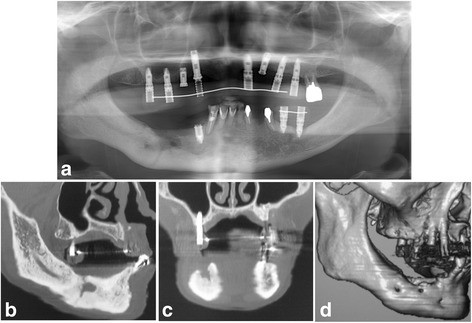

Fig. 3.

a Panoramic radiograph showing the sequestrum separation after 5 months of teriparatide therapy (arrows). b Sagittal CT view. c Coronal CT view

In April 2012, after 5 months of teriparatide therapy, the sequestrum separation had progressed (Fig. 3), and a sequestrectomy was performed under general anesthesia (Fig. 4). At 5 months after the operation, a CT scan revealed new bone formation around the bone defect in the region of the sequestrectomy, with all symptoms including bone exposure disappearing (Fig. 5). The patient’s osteoporosis treatment was continued, and 16 months after the sequestrectomy, further new bone formation was observed (Fig. 6).

a Panoramic radiograph 16 months after the sequestrectomy. b Sagittal CT view. c Coronal CT view. d 3D CT view